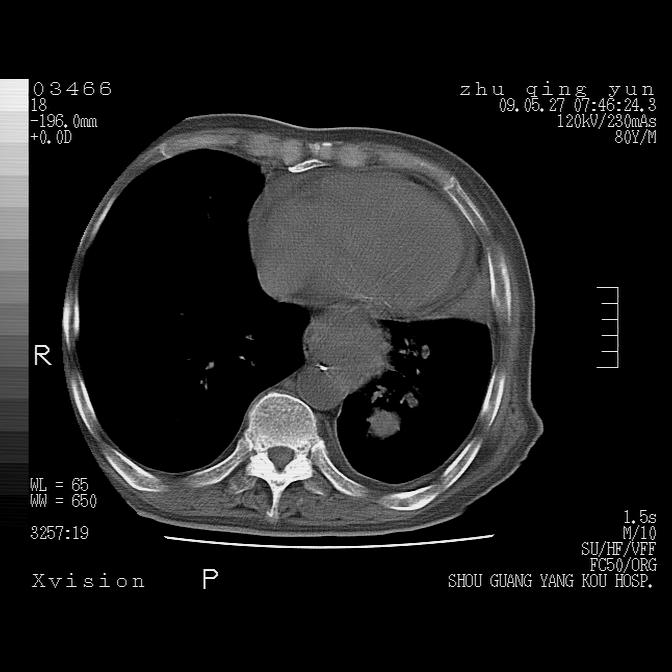

病人男性,年龄80,气喘来院,其他病史不太详细,1月前有过恶心,呕吐,在当地人民医院做过钡餐,诊断胃炎,

1)考虑左肺中央型肺癌并阻塞性肺炎,后下纵隔受侵伴纵隔淋巴结转移。2)双侧少量胸腔积液,胸膜增厚。3)心包积液。

左侧中心型肺癌并纵隔淋巴结广泛转移.心包积液

1)考虑左肺中央型肺癌并左肺下叶阻塞性肺炎、不张;左胸膜腔积液、心包积液、纵隔淋巴结转移;癌肿累及左心房。2)左心室大。冠状动脉壁钙化斑。

恶性占位是肯定的,并累及心包并纵隔淋巴结转移/左肺癌性淋巴管炎/肺部感染。是中心性或纵隔型肺癌,还是后纵隔恶性占位,还是食道中下段癌或食道受累需鉴别。